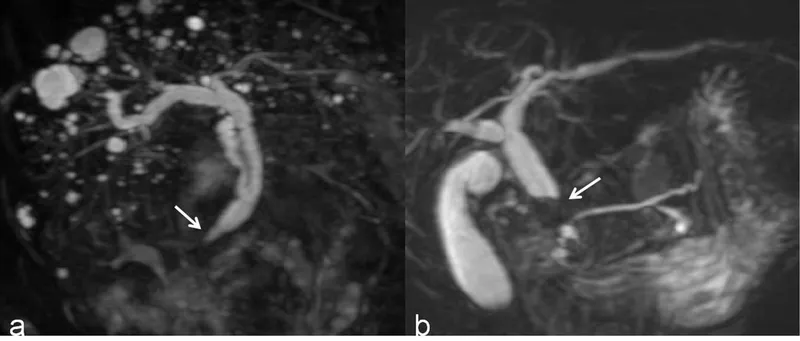

Gallbladder and Biliary Tract Diseases Indian Medical PG Question 10: The following procedure is performed for the management of?

- A. Gallbladder carcinoma

- B. Distal cholangiocarcinoma (Correct Answer)

- C. Chronic calcific pancreatitis

- D. Advanced gastric carcinoma

Gallbladder and Biliary Tract Diseases Explanation: ***Distal cholangiocarcinoma***

- The image shows a **Pylorus-preserving Whipple procedure (PPPD)**, which involves resection of the pancreatic head, duodenum, gallbladder, and part of the common bile duct, followed by reconstruction.

- This procedure is primarily performed for malignancies of the **pancreatic head**, **distal bile duct (cholangiocarcinoma)**, and **ampulla of Vater**, as they often cause obstructive jaundice and are resectable.

*Gallbladder carcinoma*

- While gallbladder carcinoma can involve the bile ducts, this specific reconstruction (PPPD) is more commonly associated with tumors of the pancreatic head or distal bile duct rather than the gallbladder itself, which might be managed with a **cholecystectomy** and possibly **liver resection**.

- The type of resection and reconstruction varies significantly based on the extent and location of gallbladder cancer.